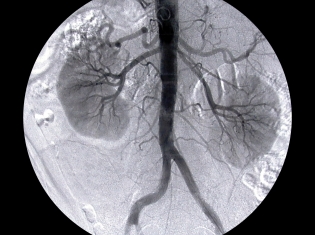

In a recent study, magnetic resonance imaging (MRI) and ultrasound revealed the potential for major cardiovascular problems in people with unusual fatty and calcium build-up in the main neck arteries that pump blood to the brain.

Dr. Bluemke and his team of investigators performed MRIs and ultrasounds on the carotid arteries — the large vessels located on each side of a person’s neck — of 946 patients from the Multi-Ethnic Study of Atherosclerosis (MESA). None of those individuals showed symptoms of stroke, heart attack or angina (chest pain) or had a history of cardiovascular disease.

The MRI identified whether patients’ arteries were clogged with plaque and what was the biological make-up of that plaque. The ultrasound measured plaque thickness. Also, the tests aimed to determine how likely it was that those plaque-hardened arteries would burst.